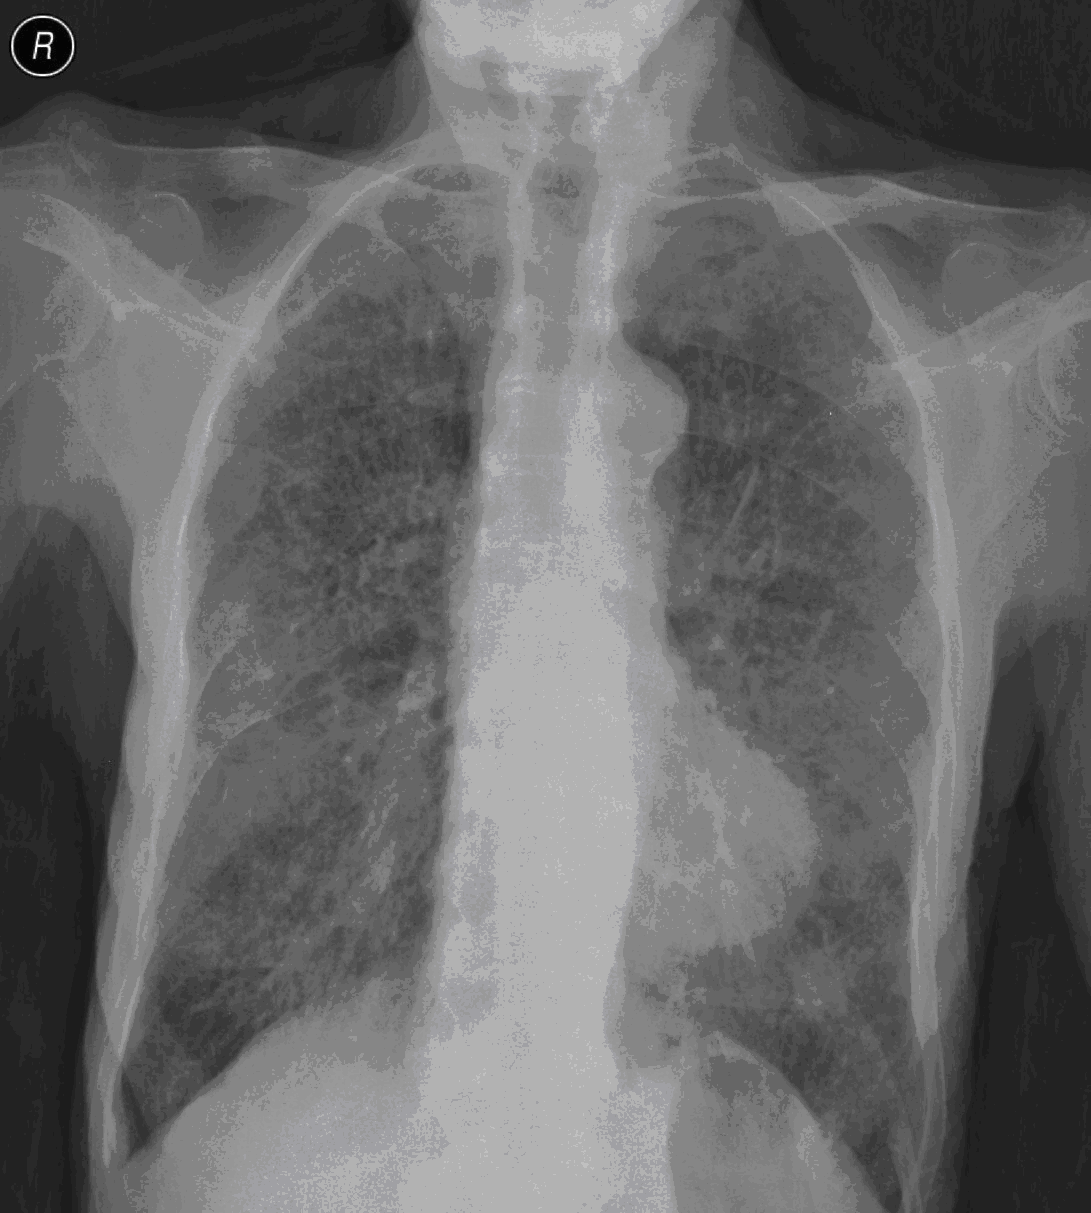

19. Tuberculosis, bidirectional chest radiographs and HRCT. (coronal reconstruction)

75 year old man: hx of hypertension, smoking. Symptoms: dyspnea, productive cough. Moist rales of auscultatory findings above the LLL, tension irritability in the level of lower dorsal spine.

a.) Chest radiograph, bilateral: Mild increased vascular markings. Extensive patchy lobar infiltration in the RUL Previous TB specific lesions in the left apex. The diaphragm contour is blurry on the right side (appr. 4 finger-wide pleural effusion). Cardiomegaly. Medium large dilated sclerotic aorta.

b.) HRCT: Reticular pattern of 10x10x5 cm area in the right apex (1st segment), (septal thickenings), mosaic-like ground glass opacity in the righ apex. Subpleural total atelectasis (mainly 1st segment): irregular mainly nodular soft tissue streak associated with the pleura (max. appr. 1 cm thickness). Some tiny subpleural emphysematous bullae in the right apex.